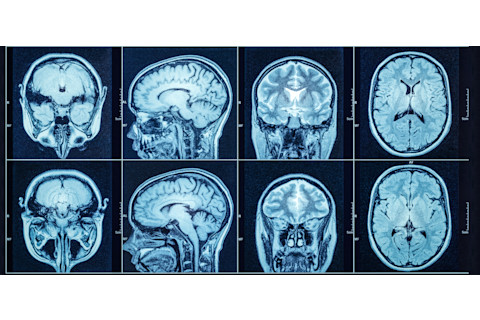

(图片来源: Triff/Shutterstock)

Triff/Shutterstock

由于 SPS 的罕见性和症状与其他疾病(如多发性硬化症)的相似性,诊断 SPS 具有挑战性。除了考虑患者表现出的症状外,医生还可以通过以下检查来帮助确诊 SPS:

高级影像学检查

可能使用大脑、脊柱、神经和其他身体部位的 MRI、PET 和 CT 扫描来帮助排除其他可能的疾病,包括多发性硬化症。